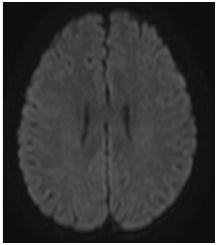

Two days after aminophylline was started, there was improvement of areas with high DWI signal. Four days later, the patient recovered movements on the face and upper limbs. In the two- week follow-up, demonstrated areas of high signal in T2 in correspondence previous areas of change of signal in DWI. (Figures 6‒8).

Figure 6 (DWI) No more identification of the focal areas of restricted diffusion in both centrum semiovale.